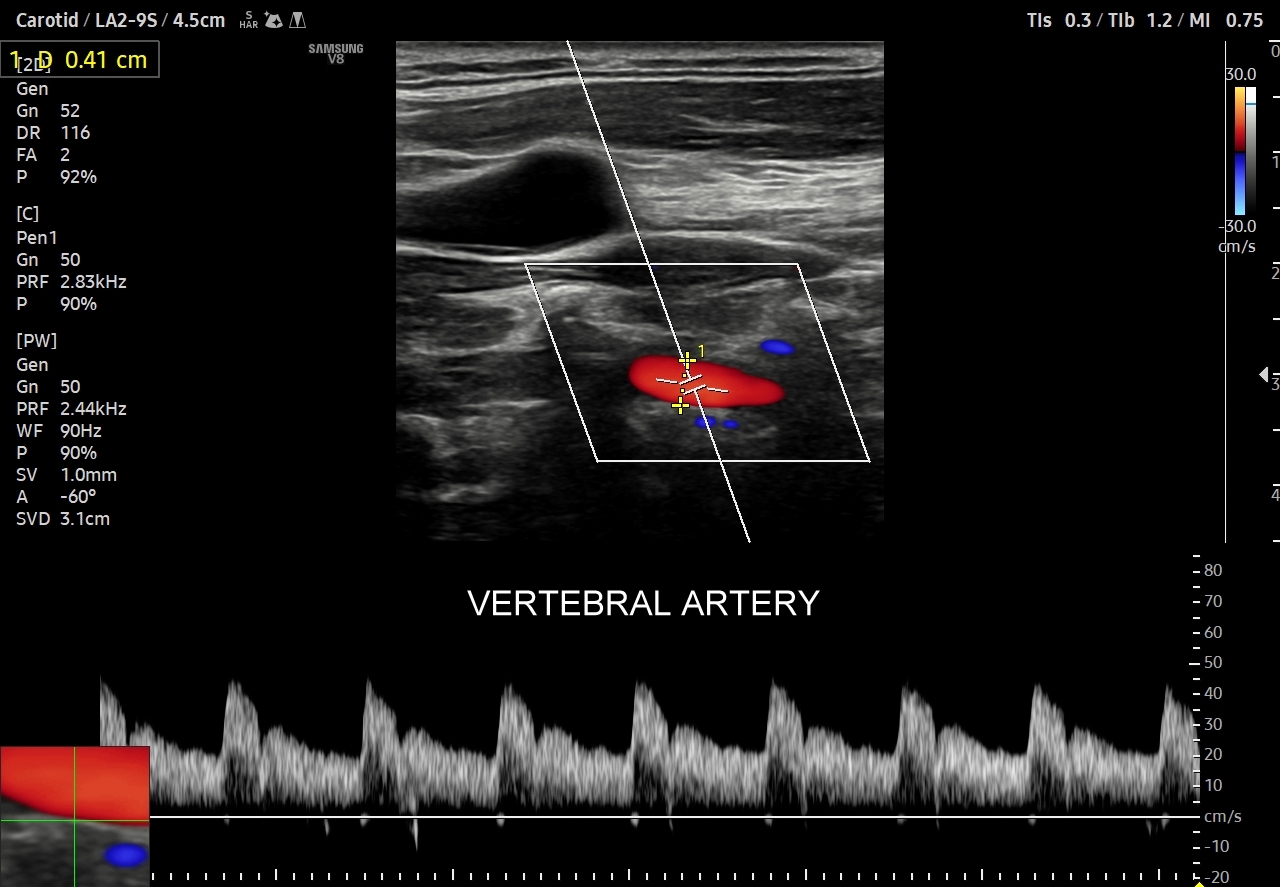

Oprócz przepływów typowo niskooporowych oraz typowo wysokooporowych istnieją profile przepływów o pośredniej charakterystyce, np. w tętnicy szyjnej wspólnej. Z kolei w przypadku tętnic kręgowych w zależności od ich szerokości fizjologicznym jest obserwowanie zarówno profilu niskooporowego w przypadku dużej średnicy, jak i wysokooporowego w przypadku małej średnicy.